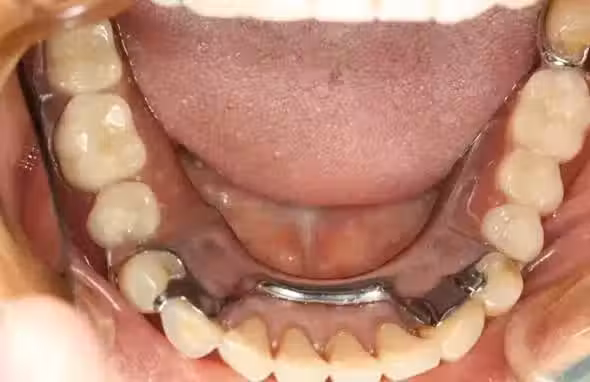

當看到牙醫時,你的問題來了──假牙還是植牙?

其中,活動假牙又叫全口義齒,屬於「鑲牙」,而鑲牙的另一種則是固定假牙(烤瓷牙)。

由於價格與功效居中,暫不討論,今天僅以價格最低的假牙和價格最高的植牙作比較,來揭秘牙醫沒對你說的那些事兒。

植牙未見得比假牙好

植牙是缺牙時的治療方式之一,但非首選,是沒有辦法的最終選擇。

國內外有別,國外高水準國家的傳統假牙治療費用比植牙還貴;但國內卻相反,假牙水準普遍不如國際水準,植牙收費較高。

利益的驅使下,便會使勁鼓吹植牙,造成浮濫。